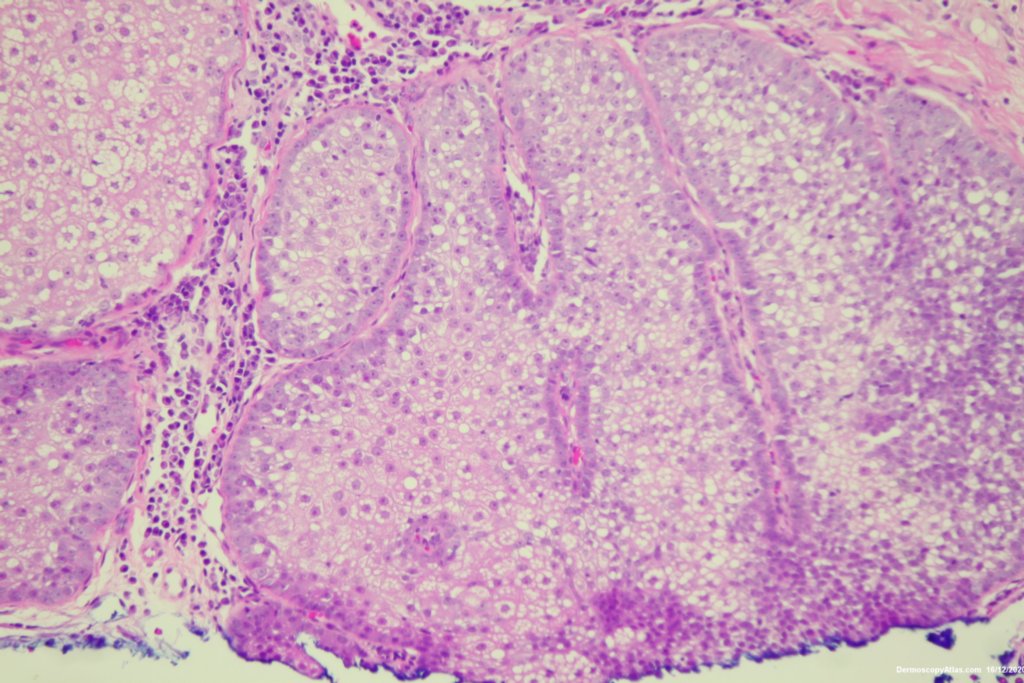

Site: Cheek

Diagnosis: Lentigo Maligna

Description: Pigmented lesion cheek and pink nodule

Elderly male with no past history of melanoma developed these two lesions over a year or so. The lentigo maligna was easy to diagnose on the clinical and dermatoscopy but the nodule was more difficult. Was it an amelanotic melanoma, BCC or SCC were the initial thoughts. Histology showed a well differentiated sebaceous carcinoma. The two lesions were excised in the same specimen with 5 mm margins. Studies failed to show the mutation for the Muir Torre syndrome which can be seen with sebaceous carcinoma.